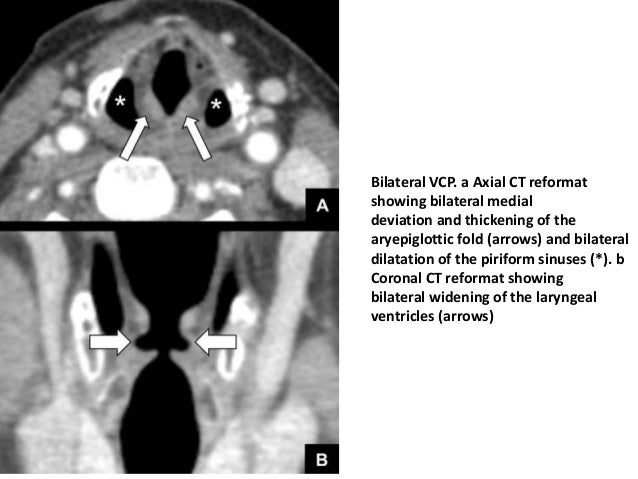

Imaging And Pathology Of Larynx (2)

larynx cartilage arytenoid dislocation vcp mimic vocal

Imaging and pathology of larynx (2). Anatomy oropharynx physiology ii memrise. Vocal cord paralysis